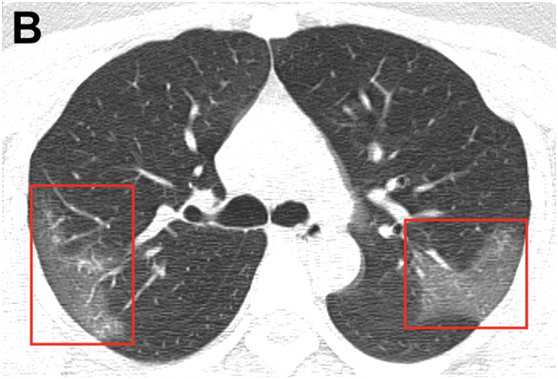

图B:经过三天的治疗,并结合干扰素吸入,该患者临床表现更差,复查胸部CT显示右上叶后段及左上叶顶端后段进行性毛玻璃样混浊。

研究指出,影像学检查是2019-nCoV诊断的关键组成部分。双侧对称的肺周混浊是2019新型冠状病毒肺炎的常见CT表现。早期疾病识别不仅对及时治疗至关重要,而且对患者隔离和有效的公共卫生控制和应对也至关重要。